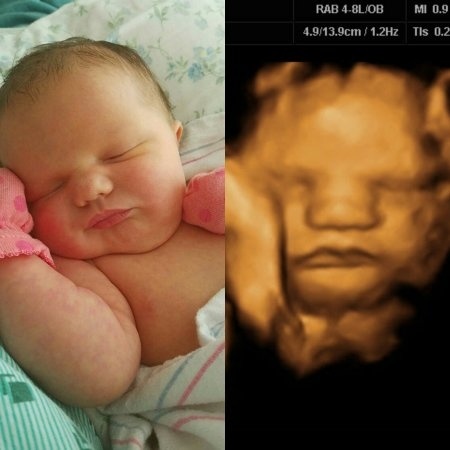

Înainte și după naștere: 10 ecografii reproduse în prezent